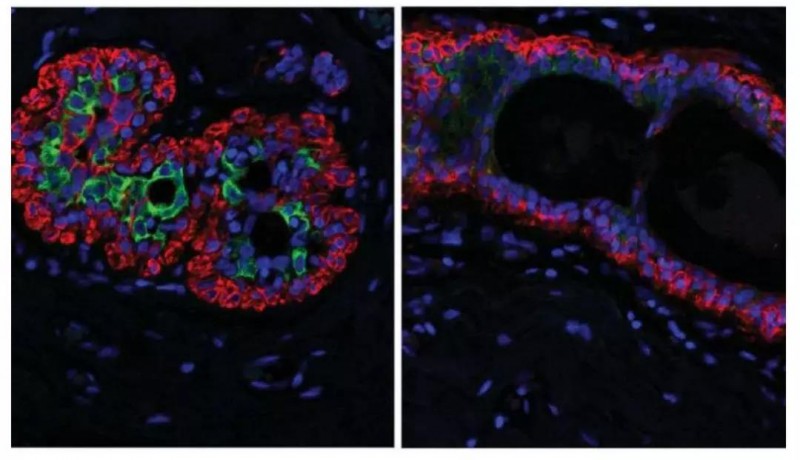

女性随着年龄的增长,其乳房组织会发生变化。多能祖细胞能够发育成多种类型的细胞,定植于身体各部位,研究人员提出祖细胞可能是癌症发生的原因。由卑尔根大学生物医学教授James Lorens领导的国际小组研究了56名女性的细胞,发现随着受试者年龄增加,多能祖细胞在乳腺组织上皮层积聚,发展成为有缺陷的管腔(内部上皮)细胞。这些有缺陷的管腔细胞看起来更像肌上皮(外)细胞,使整个管腔层的外观不太一致。同时,抑制肿瘤的肌上皮细胞比例减少。

该团队证明了年龄相关的官腔细胞是由有缺陷的官腔祖细胞衍生出来的,这些官腔祖细胞也随着年龄增长而积累,这项研究让我们更深入地了解随着年龄发生的变化,并显示出包括乳腺上皮细胞的异质性。还能鉴定出衰老的乳腺细胞中出现的蛋白质标签,这一发现可能与老年妇女对乳腺癌的易感性增加直接相关。